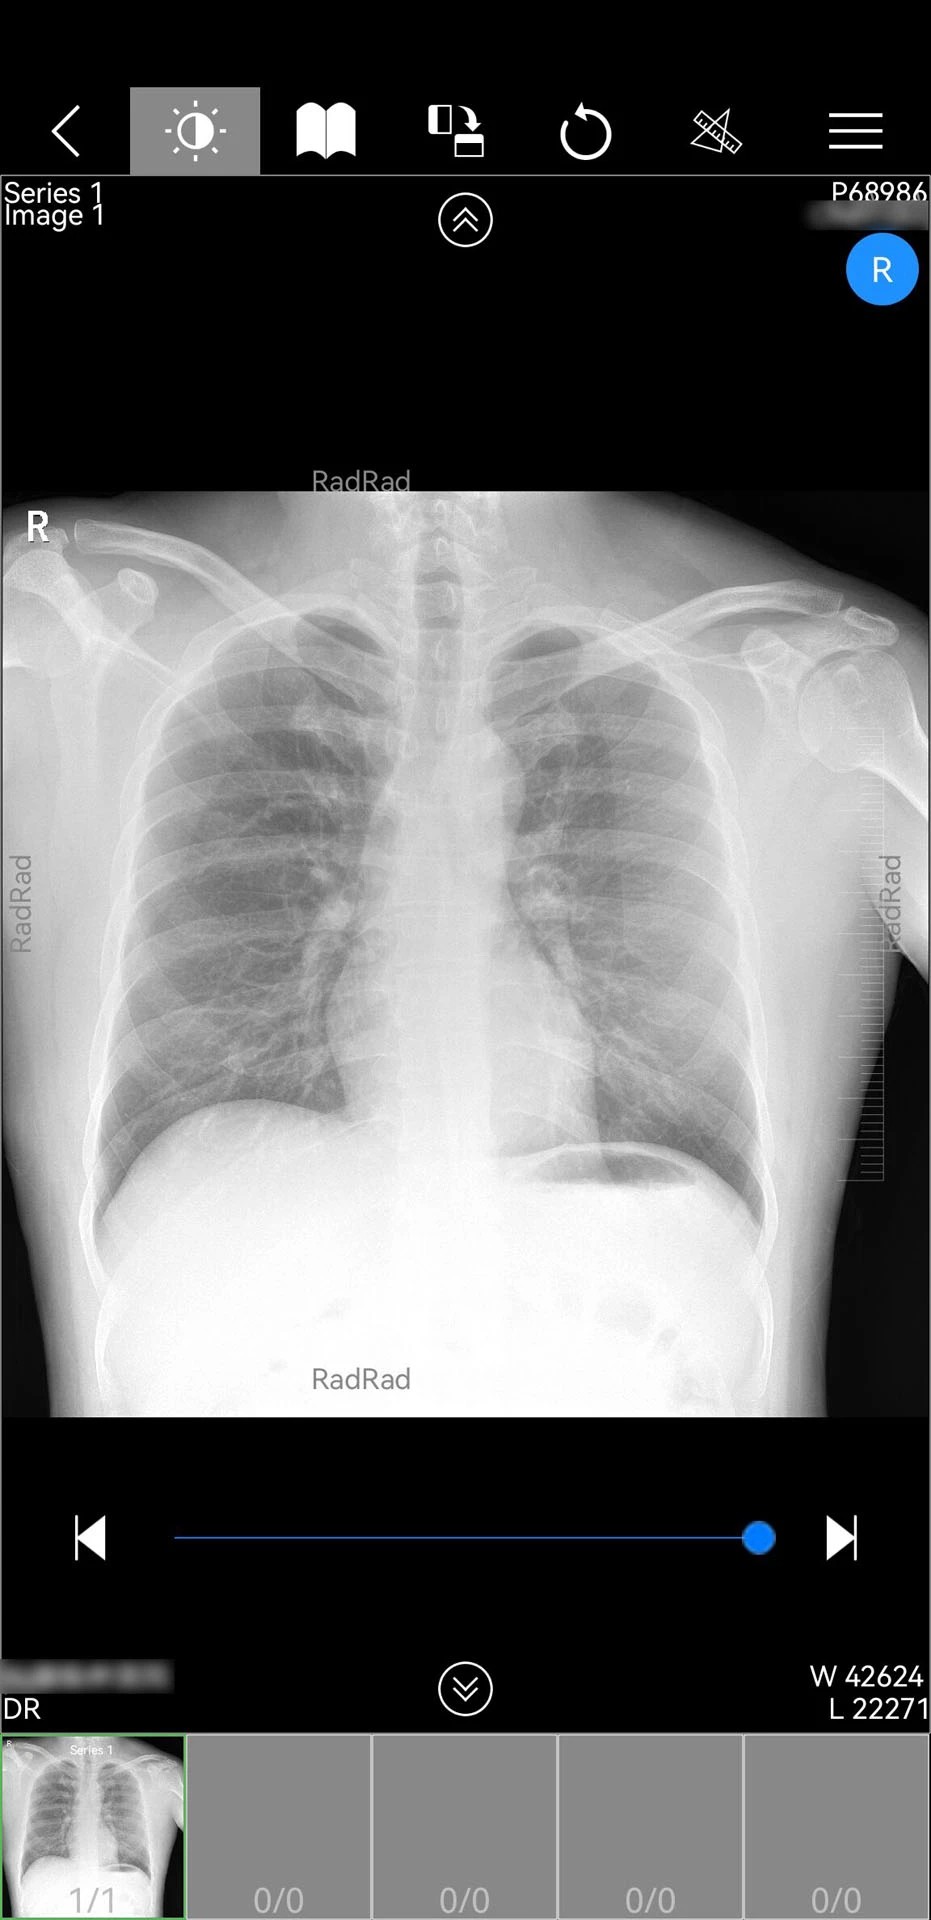

微影医生2026最新版是一款专为医护人员设计的移动医疗应用,基于Android平台开发,深度整合云服务器技术,实现患者影像数据、检查报告的实时调阅与多端共享。该版本在原有功能基础上强化了AI辅助诊断、跨院协作及隐私保护能力,支持CT三维影像处理、多模态数据融合分析等前沿功能,成为影像科医生、全科医生及医联体协作的核心工具。其全中文可视化界面与智能手势操作显著提升使用效率,日均处理超10万份影像数据,助力医疗机构实现数字化转型。

1. 影像处理性能升级:新增CT三维重建模块,支持DICOM格式原始数据直接生成3D模型,医生可通过旋转、缩放、分层查看病灶结构,辅助制定精准手术方案。例如,在肺部结节诊断中,三维模型可清晰显示结节与血管的毗邻关系,降低穿刺风险。

2. AI辅助诊断系统:集成深度学习算法,可自动识别肺结节、骨折、脑出血等常见病变,并标注关键特征(如结节大小、密度、边缘形态)。在测试数据中,AI对肺结节的检出率达98.7%,与资深放射科医生诊断结果一致性超过95%。

2. 数据接入方式:支持与医院PACS系统、区域影像平台对接,自动同步患者检查报告;也可通过手动上传DICOM文件或拍照识别纸质报告进行数据录入。

3. 操作界面设计:采用“工作台+导航栏”布局,核心功能(如影像调阅、患者管理、问诊)置于首页,次要功能(如健康评估、用药指导)通过底部标签切换。界面符合《移动医疗应用设计规范》,误操作率低于0.3%。